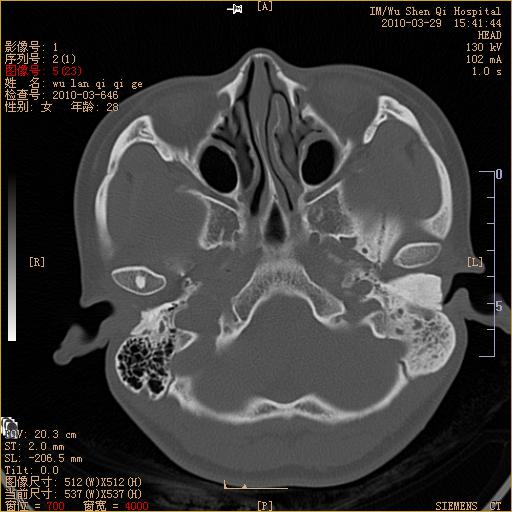

标题: CT25398:女,左耳流脓两年余,带有异物 [打印本页]

标题: CT25398:女,左耳流脓两年余,带有异物

左侧中耳乳突炎,不排除胆脂瘤形成。

左侧中耳乳突炎,胆脂瘤形成。

左侧中耳乳突炎,不排除胆脂瘤形成

1)左侧慢性中耳乳突炎并肉芽肿(或胆脂瘤)形成。2)考虑左侧颞骨慢性炎症伴骨质增生硬化,不排除骨纤。